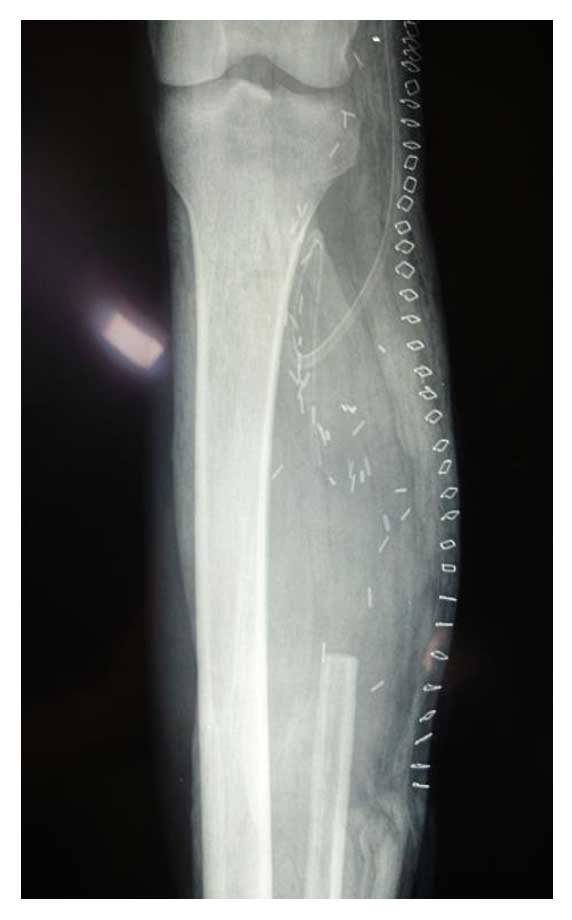

Ameliyat Sonrası: Röntgende proksimal fibula rezeksiyonu görülmekte.